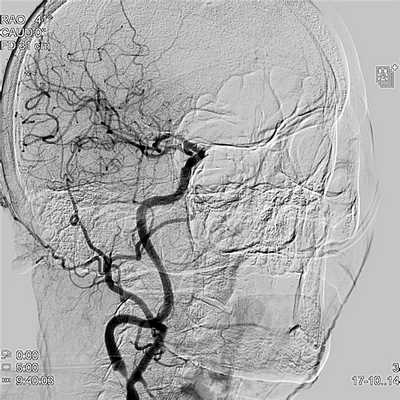

После пережатия НСА формировался проксимальный анастомоз по типу конец в бок между начальным отделом НСА и графтом (рис. 3). После снятия зажимов проводился контроль кровотока по шунту и СМА с помощью допплерографии, флуометрии и видеоангиографии с индоцианиновым зеленым (ICG-VA) с временным пережатием ВСА в области устья (рис. 4). При сохранении адекватного кровотока по интракраниальным артериям выполняли лигирование ВСА в устье и ушивание операционных ран. В 1-е сутки после вмешательства всем больным выполняли контрольную МСКТ-ангиографию экстра- и интракраниальных сосудов (рис. 5). В ближайшие часы после операции ВСА в экстракраниальном отделе тромбировалась до уровня отхождения глазничной артерии без развития неврологической симптоматики (рис. 6).

Рис. 3. Формирование проксимального анастомоза между НСА и аутоартериальным шунтом. Рис. 4. Интраоперационный контроль (ICG-VA). Стрелкой указан дистальный анастомоз. Рис. 5. МСКТ-контроль дистального анастомоза. Стрелкой указан дистальный анастомоз между М2 сегментом СМА и аутоартериальным шунтом. Рис. 6. МСКТ-контроль после операции. Отмечается отсутствие контрастирования ВСА в экстракраниальном отделе. Стрелкой указан высокопотоковый экстраанатомический шунт НСА-СМА (High-flow EC-IC bypass).